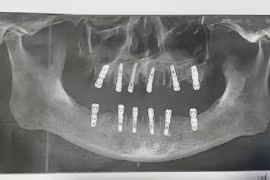

Tử vong sau khi nhổ 23 răng, cấy ghép 12 răng chỉ trong một ngày

Cái chết của một người đàn ông Trung Quốc xảy ra 13 ngày sau khi được nhổ 23 cái răng và cấy ghép (implant) 12 cái chỉ trong một ngày đã gây chấn động Trung Quốc, theo SCMP.